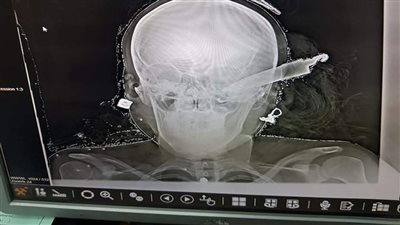

فريق طبي بمستشفى جامعة سوهاج ينقذ شخصًا من الموت بعملية استغرقت 7 ساعات (صور)

السبت 08/05/2021 06:24 م

على طريقة "ساطور سوهاج".. إنقاذ سيدة مضروبة بسكين في رأسها بالمنوفية (صور)

الثلاثاء 06/04/2021 10:07 م

طبيب إصابة الساطور يكشف تفاصيل جديدة عن الحالة (فيديو)

الثلاثاء 23/03/2021 09:10 م